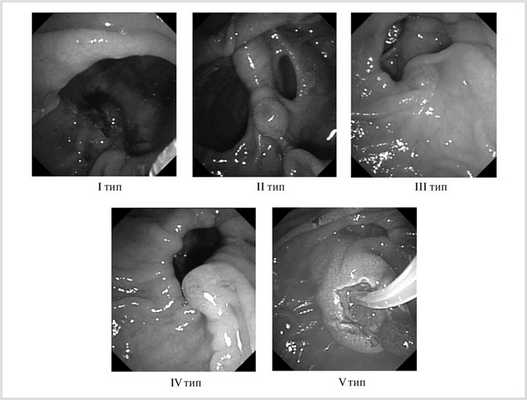

Проанализирован опыт чреспапиллярных вмешательств у 2516 пациентов с подозрением на холедохолитиаз, находившихся на лечении в ККБ № 1 им. С.В. Очаповского с 2010 по 2015 г. У 423 (16,8%) больных, в том числе 121 (28,6%) мужчины и 302 (71,4%) женщин, при выполнении дуоденоскопии были выявлены дивертикулярные изменения медиальной стенки нисходящей части ДПК. Основными показаниями к проведению вмешательств были клинические и ультразвуковые признаки холедохолитиаза и других осложнений желчнокаменной болезни. Механическая желтуха была выявлена у 288 (68,1%) больных, причем только у 96 (22,7%) пациентов уровень билирубина превышал 100 мкмоль/л. Во время эндоскопического исследования особое внимание обращали на анатомические взаимоотношения БСДК, продольной складки ДПК и дивертикула, так как руководствовались классификацией, предложенной И.В. Громовой и соавт. [3], в основе которой лежит взаимозависимость их расположения (рис. 1).

Рис. 1. Типы парапапиллярных дивертикулов по классификации И.В. Громовой и соавт.

В 65 (15,4%) наблюдениях нами был выявлен I тип дивертикулов, при котором БСДК располагается в полости дивертикула, в 17 (4%) — II тип — БСДК располагается между двух дивертикулов, у 124 (29,3%) — III тип — БСДК располагается в области шейки дивертикула или за его пределами, при этом продольная складка ДПК переходит на стенку дивертикула, у 145 (34,3%) — IV тип — устье БСДК и продольная складка ДПК располагаются в области шейки дивертикула, у 72 (17%) — V тип — БСДК и продольная складка ДПК находятся за пределами дивертикула и его шейки.